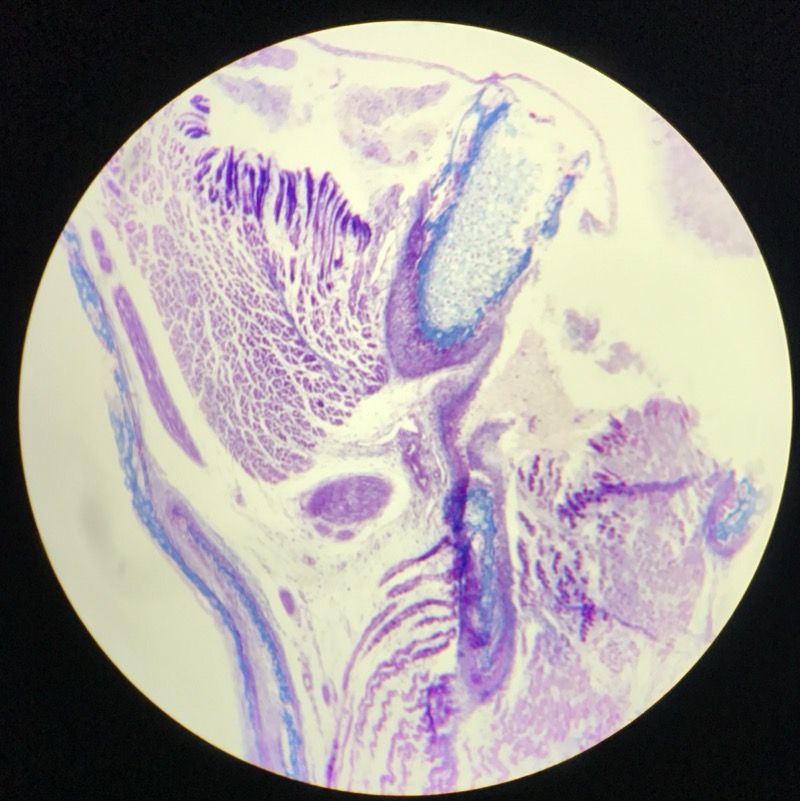

| 1:5:6 | Nagel | ![]() ![]() ![]() ![]() ![]() |